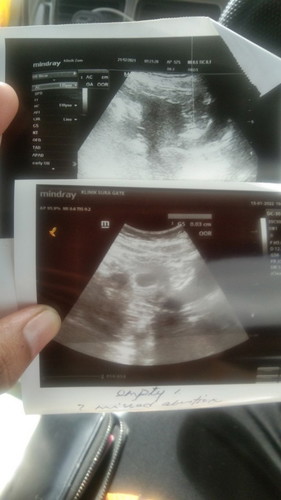

Hamil tapi kosong

Assalamualaikum dan salam sejahtera.. Saya ibu 31tahun dan mempunyai anak 2orang, anak saya yg kecil berumur 6tahun. Saya pernah ada sejarah keguguran tahun lepas dan kini hamil semula.. Saya last datang haid 9/11/21, bulan 12 saya tidak dtg terus haid dan saya buat upt 12/12/21 samar² , esokkan saya test pulak 13/12/21 samar² juga dan 19/12/21 saya test pulak terang double line saya senyum sampai ke telinga.. Sy pon rujuk ke doktor scan tidak nampak lansun dan doktor bagi tarikh 2mggu lagi untuk scan balik. Masuk tahun baru lebih pada tarikh 2mggu smalam 14/1/22 saya sedar di seluar dalam saya ada tompok coklat. Hari ni 15/1/22 saya pon rujuk klinik doktor lain dan scan dalam kantung saya kosong.. Saya rasa terkejut sngt.. Doktor bagi pulak tempoh 1mggu lagi. Soalan 1. Saya bingung adakah saya ada harapan lagi atau tidak? Penantian suami saya penuh harapan.. 2. Adakah saya kene cuci atau tgu keguran semula jadi?